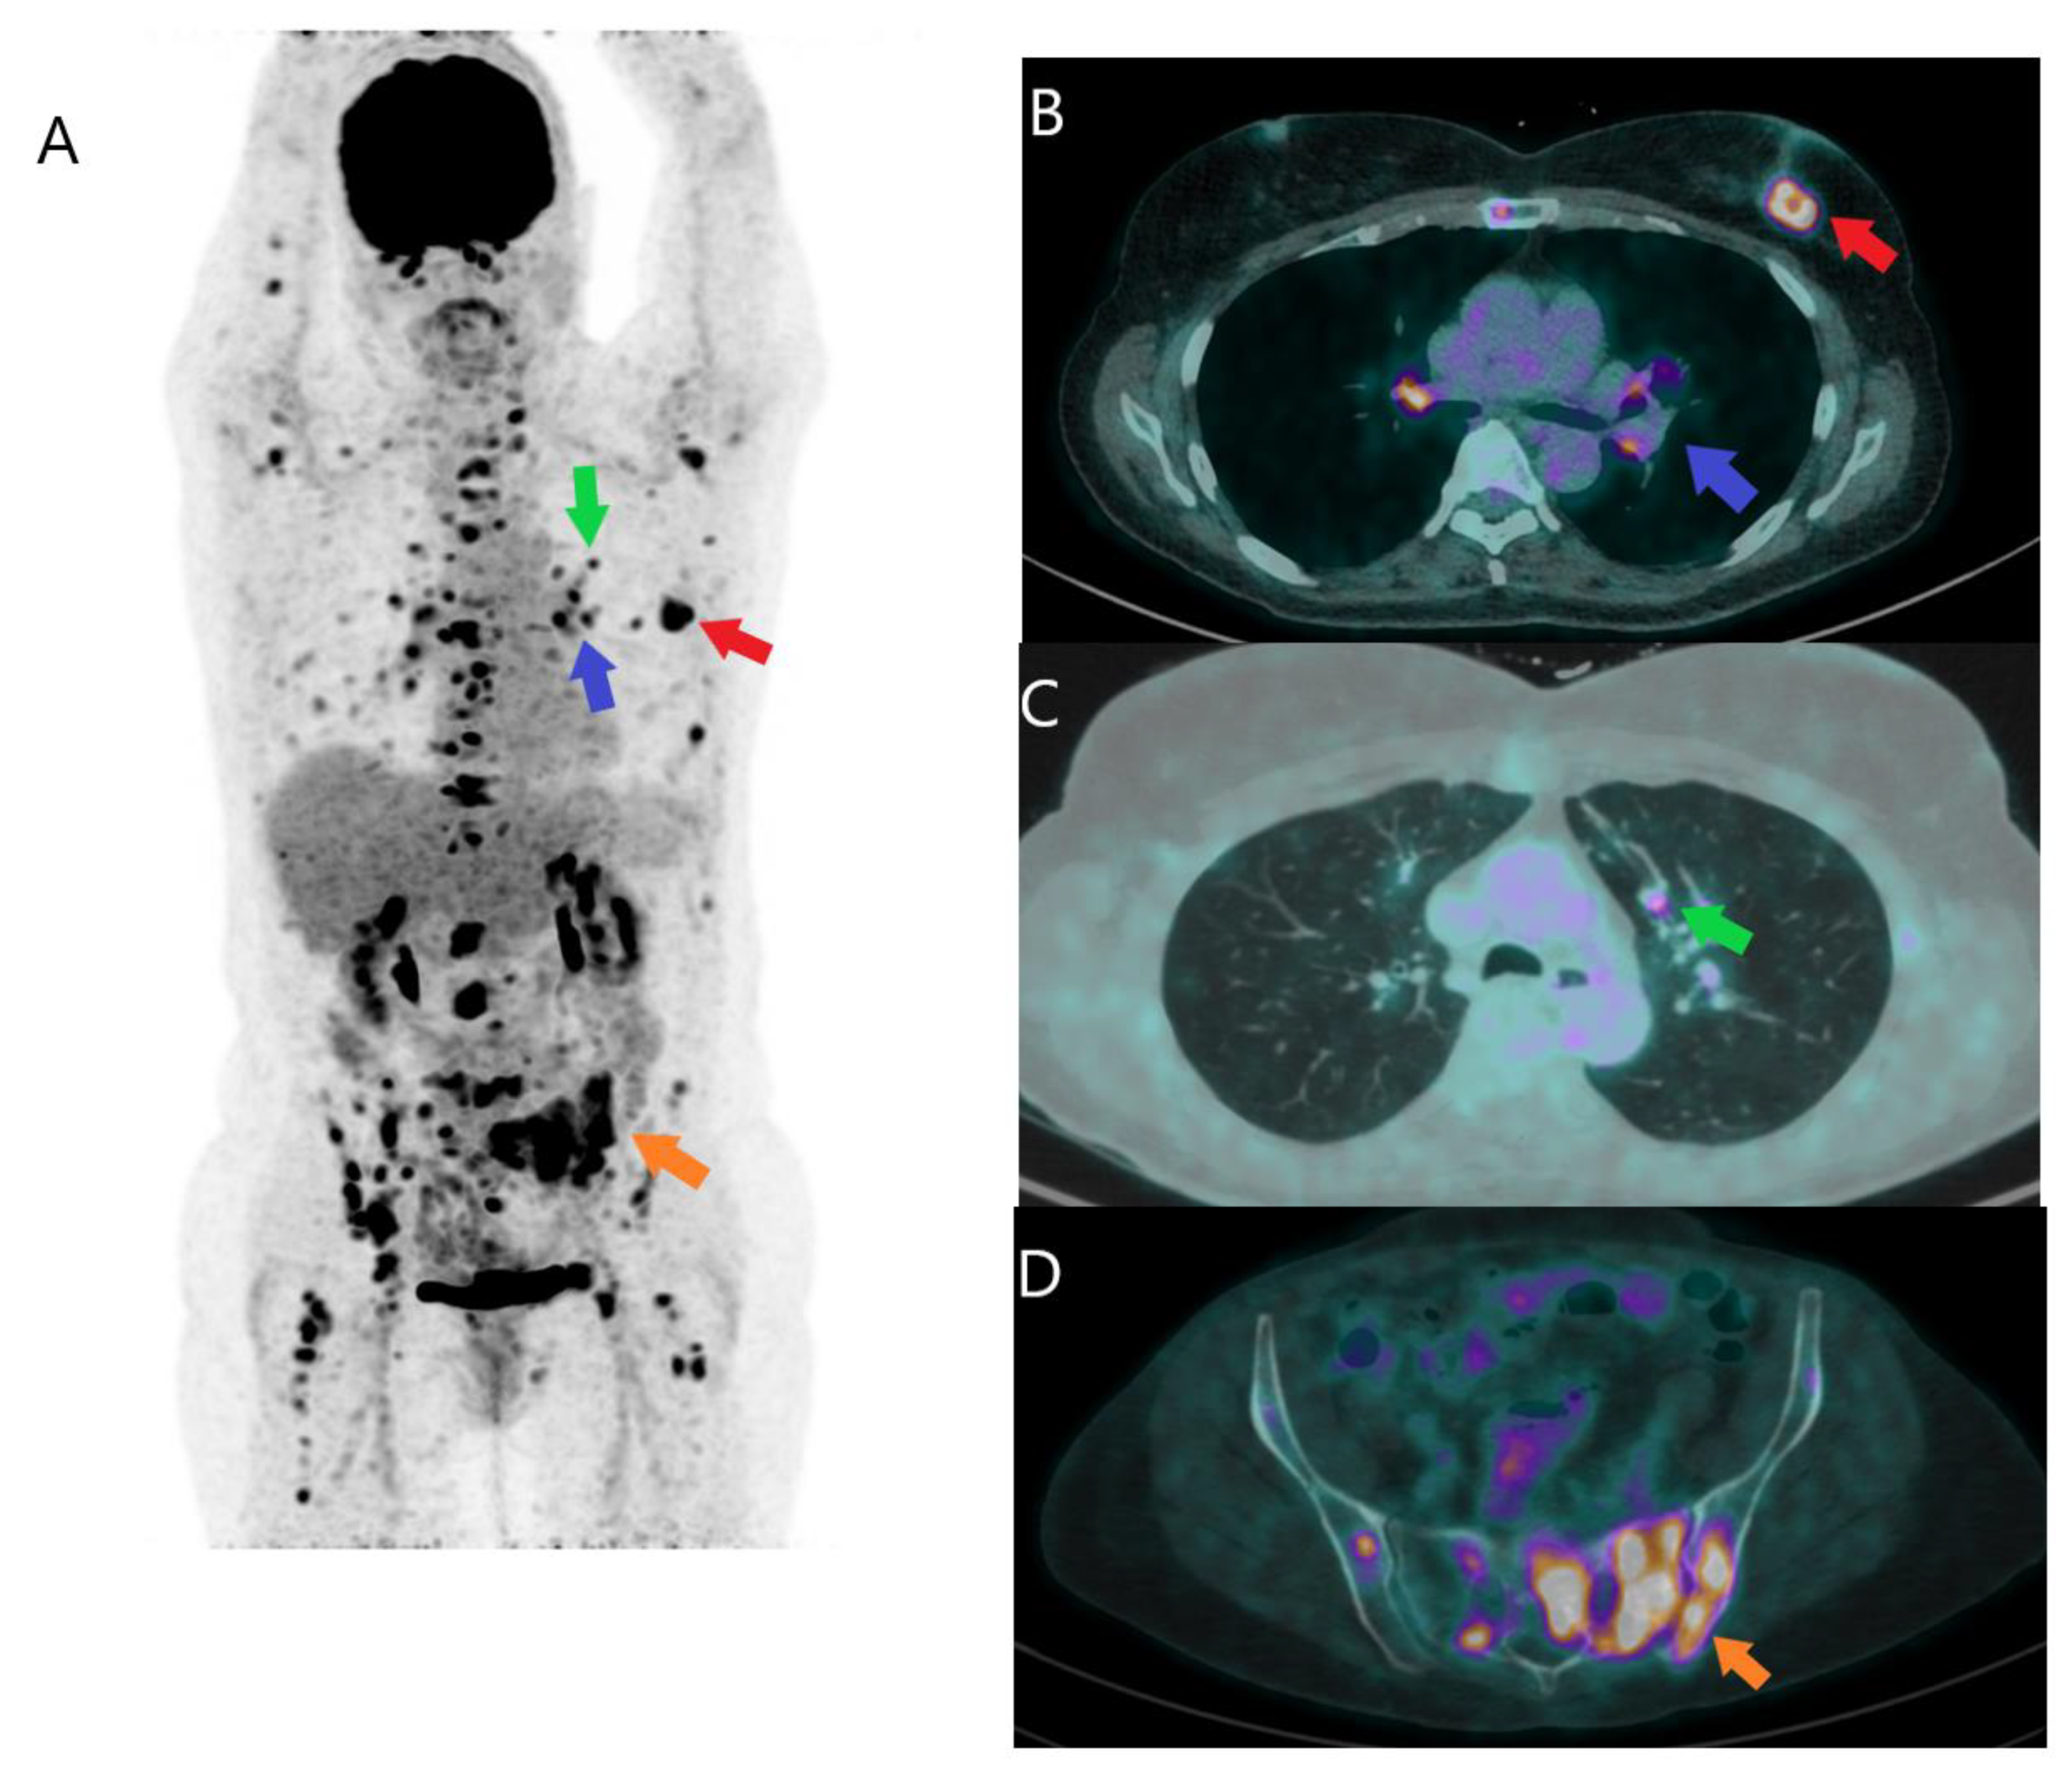

2.1.3. Initial Detection of Distant Metastases

2.2. Recurrent Disease